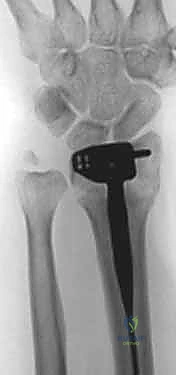

3. الكسور المعقدة التي تتطلب شريحتين (Dual Plating): في بعض الإصابات البالغة، قد يستخدم الدكتور هطيف شريحة بطنية وأخرى ظهرية لضمان استقرار مطلق للمفصل.

4. وضع الشريحة والتثبيت بالمسامير

بمجرد أن يصبح العظم في موضعه الصحيح، يتم وضع الش